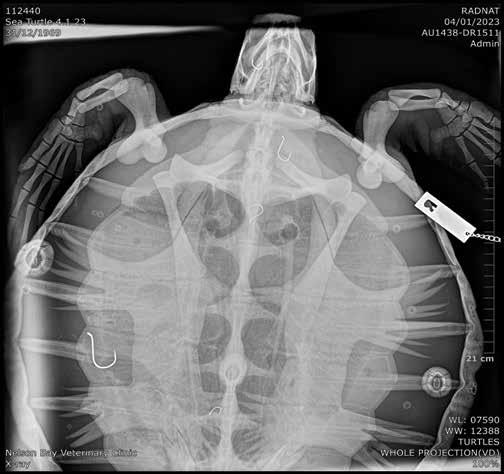

Rescued sea turtle ‘5 Hooks’ returned to ocean home

ingesting a fishhook, has now been rehabilitated and released back into the ocean.

Sea Shelter wildlife rescuers were alerted to

the plight of the turtle by members of the public.

“A couple of young boys had been fishing when they actually hooked the turtle and

pulled it in,” said Lia Pereira, marketing manager and part of the marine rescue team for Sea Shelter, the ocean conservation group affiliated with Irukandji Shark and Ray Encounters.

“They were unsure as to what to do next, but fortunately we were nearby when they contacted us.”

The experienced team promptly rescued the animal and took it to Nelson Bay Vet for assessment, where radiographs were collected to determine where the hook was lodged.

“We were so shocked to discover that she had not one but five hooks lodged at various positions within the gastrointestinal tract,” said veterinarian Dr Kathryn Stalder.

“She was at significant

risk of life threatening obstruction and intestinal rupture.”

The turtle was transported to Taronga Zoo for treatment and rehabilitation.

The expert veterinary team at Taronga Wildlife Hospital were able to nurse the turtle back to health and successfully release her with the assistance of NSW Police Maritime unit and NSW National Parks and Wildlife on Friday 14 April.

The turtle, affectionately known as ‘5 Hooks’, has been fitted with a radio tracking device attached to her shell so that her movements and the outcome of her release can be monitored.

The Taronga Zoo Wildlife Hospital team have released a Facebook post urging anglers

to dispose of all used fishing hooks and line appropriately to minimise the risk to marine life.

“We’d like to encourage people fishing to take as much care as they can to retrieve their lines, because creatures like turtles can ingest them so easily,” Lia added.

“We also encourage all people who fish not to use stainless steel hooks as they do not degrade and remain a danger for far longer.”

If you find an injured marine animal locally, please contact the Sea Shelter team on (02) 4982 2476, or report to NSW National Parks and Wildlife.

Local vets are happy to receive and assess injured wildlife and arrange further care.

A FEMALE green sea turtle, rescued from the Nelson Bay Marina on 4 January after q The radiograph revealed five hooks throughout the sea turtle's body.

A green sea turtle has been rehabilitated and released after surviving close call with ingested fish hooks

q ‘5 Hooks’ being released.